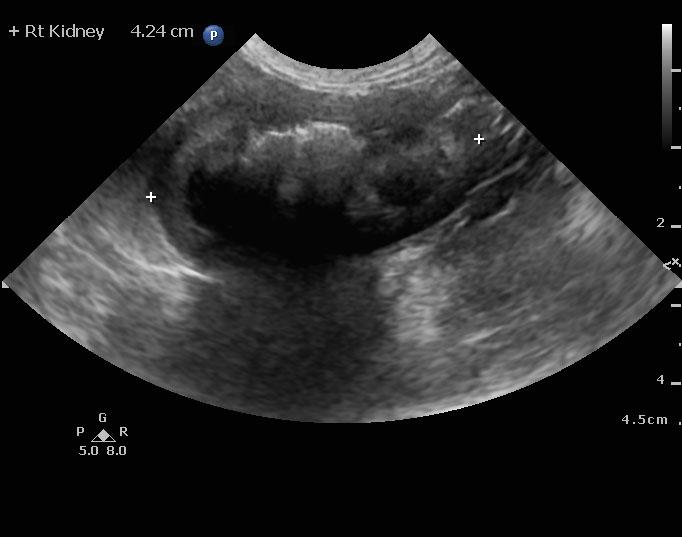

An 8-year-old spayed female Maltese dog was presented for evaluation of severely elevated pre-and post-prandial bile acids. In addition, the patient was positive for Rocky Mountain spotted fever. Seizure activity was present in the history